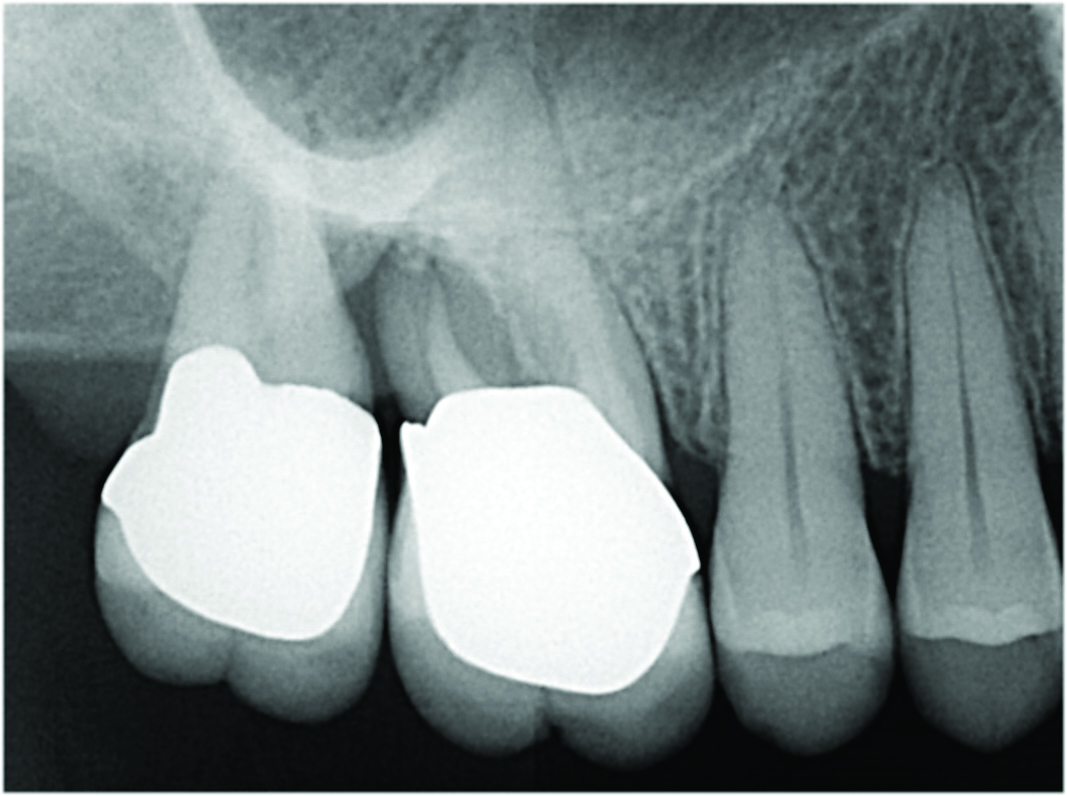

Fig 2. Examples of multirooted teeth showing periradicular periodontitis and loss of periradicular bone support isolated to one root (indicated by red arrows). Fig 1: Tooth No. 3 distobuccal root with circumferential bone loss from the crestal bone height to the apex with stable mesiobuccal and palatal roots. Fig 2: Tooth No. 30 with a prior apical surgery showing bone loss surrounding a fractured mesial root. Fig 3: Tooth No. 19 with lateral and apical bone loss regions affecting a fractured mesial root. Fig 4: 3D CBCT imaging of tooth No. 3 depicting an apicomarginal bone loss defect affecting the mesiobuccal root with stable fused distobuccal and palatal roots.

Fig 1 through Fig 4. Examples of multirooted teeth showing periradicular periodontitis and loss of periradicular bone support isolated to one root (indicated by red arrows). Fig 1: Tooth No. 3 distobuccal root with circumferential bone loss from the crestal bone height to the apex with stable mesiobuccal and palatal roots. Fig 2: Tooth No. 30 with a prior apical surgery showing bone loss surrounding a fractured mesial root. Fig 3: Tooth No. 19 with lateral and apical bone loss regions affecting a fractured mesial root. Fig 4: 3D CBCT imaging of tooth No. 3 depicting an apicomarginal bone loss defect affecting the mesiobuccal root with stable fused distobuccal and palatal roots.

Fig 1. Examples of multirooted teeth showing periradicular periodontitis and loss of periradicular bone support isolated to one root (indicated by red arrows). Fig 1: Tooth No. 3 distobuccal root with circumferential bone loss from the crestal bone height to the apex with stable mesiobuccal and palatal roots. Fig 2: Tooth No. 30 with a prior apical surgery showing bone loss surrounding a fractured mesial root. Fig 3: Tooth No. 19 with lateral and apical bone loss regions affecting a fractured mesial root. Fig 4: 3D CBCT imaging of tooth No. 3 depicting an apicomarginal bone loss defect affecting the mesiobuccal root with stable fused distobuccal and palatal roots.